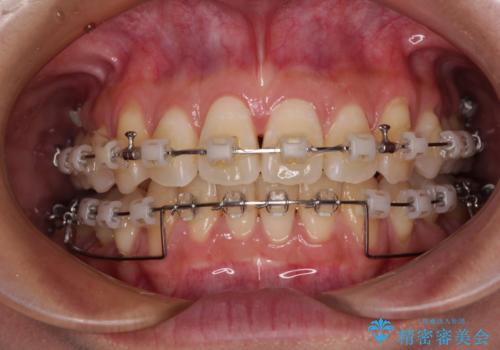

- クリアブラケット

- 1年6ヶ月

- 上顎前歯の突出感を気にして来院された患者様です。

舌の突出癖の影響で、歯列が前方に飛び出いた形態となっている状態でした。

抜歯矯正とするような歯列ではないため、舌のトレーニングを行いながら歯列を側方に拡大させることで口元の突出感を改善することとしました。